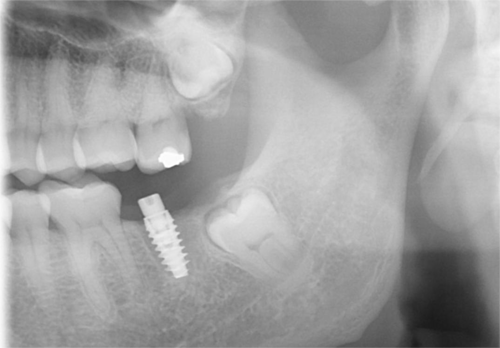

Low dose scan, high value image (Better diagnosis and treatment planning)

Getting your implant as soon as possible (after tooth loss) is the best way to reduce bone loss and avoid bone graft.

Bone loss happens immediately after you lose your teeth

Note: sinus floor will also drops down and further reduce available bone

Low Sinus Floor

Implant Placement using surgical guides for precision, the titanium implant is placed into your jawbone, typically 30-60 minutes with local anaesthesia.

A 3-6 month healing period for implant to integrate with bone (osseointegration). You’ll have a temporary solution during this time.